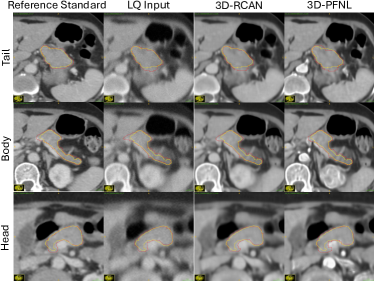

Fig. 3 shows the distribution of Dice scores and NSD for pancreas segmentation by TS on the reference (original) PV CT, low-quality (LQ) PV CT, 3D-RCAN restored PV CT, and 3D-RFNL restored PV CT, respectively. From Table II, the reference corresponded to the baseline performance of TS on the original PV CT for pancreas segmentation. However, when TS was executed on the degraded low-quality PV CT, the Dice score and NSD dropped to 68.9 19.3 and 22 8, respectively. After PV phase quality enhancement with 3D-RCAN, the Dice score and NSD improved by approximately 1.9% and 2%, respectively. Moreover, quality enhancement with 3D-PFNL further improved the Dice score by approximately 2.8% and NSD by 3%. Moreover, 3D-PFNL attained a lower standard deviation in Dice scores compared to both LQ and 3D-RCAN. The confidence interval of Dice score and NSD obtained by 3D-PFNL are [0.6299, 0.7725] and [0.2066, 0.2869] respectively.

Compared against LQ, results from 3D-PFNL on the restored PV CT were statistically significant for both Dice score (p = .034) and NSD (p = .025). The Dice score on the restored PV CT was also significant for 3D-RCAN (p = .007). Notably, TS failed to segment the pancreas in one LQ PV CT. After quality enhancement with 3D-PFNL, TS segmented the pancreas in the same volume. Fig. 4 shows an example. The pancreatic body (second row in Fig. 4) and tail (first row) tended to be over-segmented, while the pancreas head (third row) was under-segmented. After quality enhancement, TS segmented most of the pancreas with minor errors.